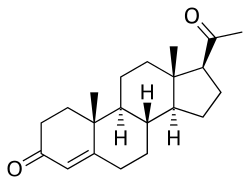

This is a list of progestogens that are or that have been used in clinical or veterinary medicine. They are steroids and include derivatives of progesterone and testosterone.

Progesterone derivatives

| Progesterone | Pregn-4-ene-3,20-dione | |